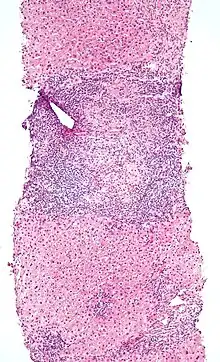

Micrograph of PBC showing bile duct inflammation and injury, H&E stain

On microscopic examination of liver biopsy specimens, PBC is characterized by chronic, nonsuppurative inflammation, which surrounds and destroys interlobular and septal bile ducts. These histopathologic findings in primary biliary cholangitis include:[32]

• Inflammation of the bile ducts, characterized by intraepithelial lymphocytes

• Periductal epithelioid granulomas.

• Proliferation of bile ductules

• Fibrosis (scarring)